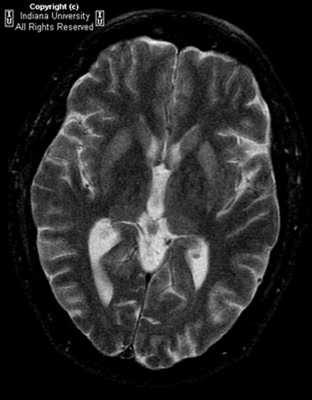

При проведении МРТ головного мозга в Т2-режиме определяется так называемый «симптом медовых сот» - участки повышенного сигнала, исходящие от подкорковых ганглиев и таламуса. Зачастую выявляются признаки атрофических изменений мозжечка и коры головного мозга, расширение желудочков и боковых цистерн мозга. ПЭТ диагностирует зоны пониженного метаболизма, локализующиеся в подкорковых ядрах, полушариях мозжечка и коре мозга.

До недавнего времени «золотым стандартом» верификации диагноза БКЯ являлась биопсия головного мозга, позволяющая выявить характерные изменения в мозговой ткани в виде мелких вакуолей в телах нейронов, из-за чего ткань мозга приобретает губчатый вид, пролиферации клеток глии при отсутствии признаков воспаления. При электронной микроскопии возможно обнаружение прионных палочек, являющихся патогномоничным признаком заболевания. Указанные морфологические изменения отмечаются в коре головного мозга, базальных ганглиях, мозжечке и верхних отделах ствола мозга. Однако в случаях БКЯ биопсия мозга не нашла широкого применения в клинической практике из-за инвазивности метода, сложности санитарной обработки оборудования и утилизации биоматериалов, связанных с высокой устойчивостью прионов, а также вследствие небольшого объема биоптата мозговой ткани, что может быть причиной ложноотрицательных результатов морфологического и иммуногистохимического исследования. Однако в настоящее все больше распространена МРТ диагностика данного заболевания, по причине выявления специфических изменений, наиболее информативными являются последовательность DWI.

На диффузионно-взвешенной (DWI) магнитно-резонансной томографии (МРТ) головного мозга выявляются аномальные билатеральные гиперинтенсивные сигналы на Т2-взвешенных изображениях (симптом «медовых сот») преимущественно в области головок хвостатых ядер, таламуса, отмечается атрофия коры больших полушарий и мозжечка [6].

- На МРТ можно выявить признаки атрофических изменений в мозжечке и коре мозга (синдром «медовых сот»), расширение желудочков. От подкорковых структур и таламуса иногда улавливаются участки с повышенным сигналом.